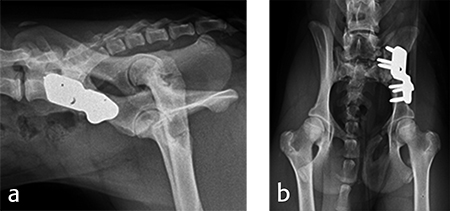

Postoperative radiographs revealed reduction in subluxation with capture of the femoral head in the right coxofemoral joint (Fig 4). Palpation of the hip revealed good stability of the right hip. Activity was restricted to leash walk only for 6 weeks postoperatively. Radiographic examination 7 weeks following surgery revealed healing of the ilial osteotomy, stable implants, and excellent coxofemoral conformation and stability (Fig 5).